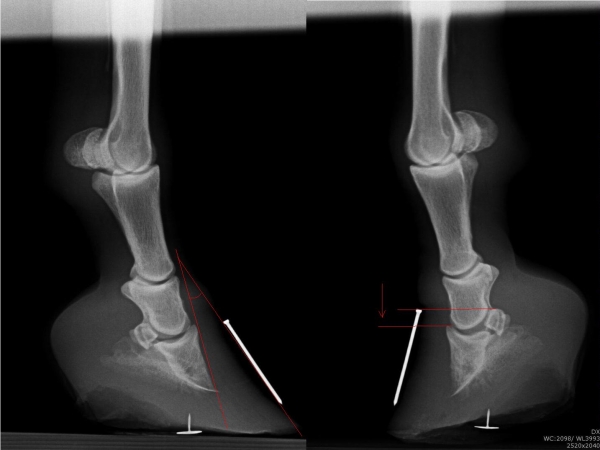

Chronicky schvácené kopyto

Sam - kladrubský hřebec s laminitídou a výhřezem kopytní škáry, teď krásně chodící a to hlavně díky velké pomoci podkováře, p.Schmidta